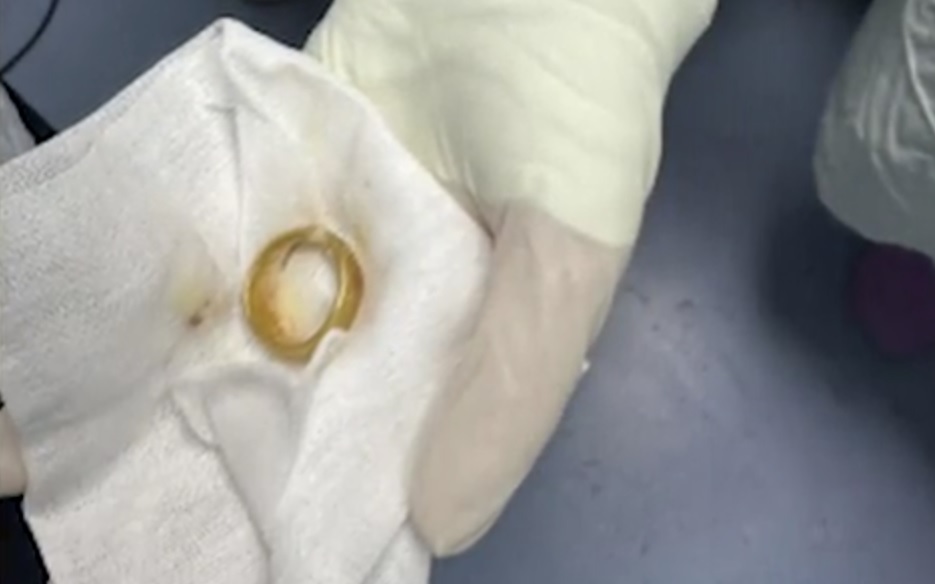

Ngày 15/3, đại điện Bệnh viện Ngoại khoa 115 Nghệ An chia sẻ với Sức khỏe & Đời sống vừa phẫu thuật thành công lấy viên sỏi bàng quang kích thước lớn cho bệnh nhân B.N.T (50 tuổi, trú tại Nghệ An).

Khai thác tiền sử bệnh trước đó, bệnh nhân đến khám trong tình trạng tiểu buốt, tiểu khó kéo dài, kèm đau vùng hạ vị. Qua thăm khám lâm sàng, siêu âm và chụp X-quang, các bác sĩ phát hiện trong bàng quang có viên sỏi kích thước khoảng 60x40 mm.

Nhận định đây là viên sỏi lớn, nguy cơ gây tắc nghẽn và nhiễm trùng đường tiết niệu, ê kíp bác sĩ đã chỉ định phẫu thuật mở lấy sỏi bàng quang.

Trong quá trình phẫu thuật, các bác sĩ rạch da đường giữa trên xương mu, tiếp cận bàng quang và lấy ra một viên sỏi lớn, kích thước tương đương quả trứng ngỗng. Sau khi lấy sỏi, bàng quang được bơm rửa sạch và khâu phục hồi theo đúng quy trình chuyên môn. Ca mổ diễn ra thuận lợi. Hiện bệnh nhân tỉnh táo, sức khỏe ổn định và đang được theo dõi, chăm sóc hậu phẫu.